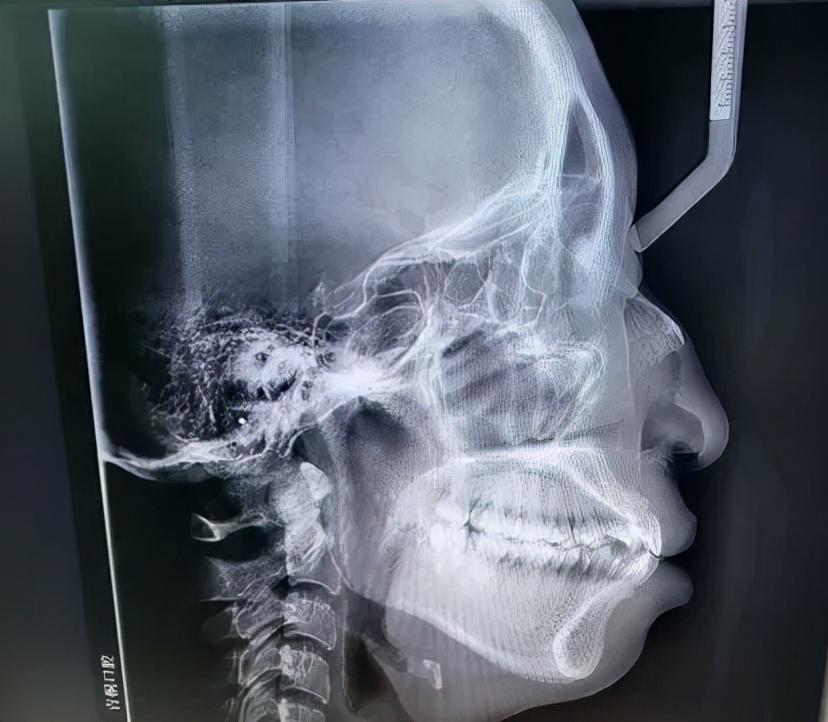

如何判斷是否屬于骨性口凸,不是光看照片或是照鏡子就能判斷的,必須要拍片檢查,通過(guò)專業(yè)的頭影測(cè)量數(shù)據(jù)才能知道。骨性外凸通常包括以下幾種具體情況。

1、上頜骨發(fā)育過(guò)度:上頜骨過(guò)度發(fā)育導(dǎo)致凸嘴。2、下頜骨發(fā)育不全:很多人認(rèn)為骨性嘴凸一定是上頜骨突出造成的,但也不一定,也有一些人的嘴看起來(lái)很凸,是因?yàn)橄骂M骨發(fā)育不全(即下頜骨后縮)。3、雙下巴問(wèn)題:當(dāng)然還有一種情況是上下頜骨都有問(wèn)題,這也是比較常見(jiàn)的一種情況,比如上頜骨突出,下頜骨發(fā)育不全(下頜骨后縮),看起來(lái)就像嘴巴突出和沒(méi)有下巴的結(jié)合體。